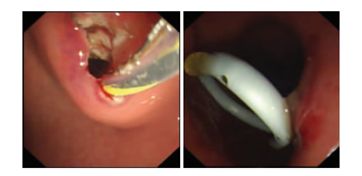

波科支架怎么样五分钟解决胰腺假性囊肿,波科AXIOS支架和电灼增强输送系统 | 盖伦奖提名医械详解Ⅹ_https://www.jmylbn.com_新闻资讯_第6张

通过胃壁穿破假性囊肿,放入2枚双猪尾塑料支架